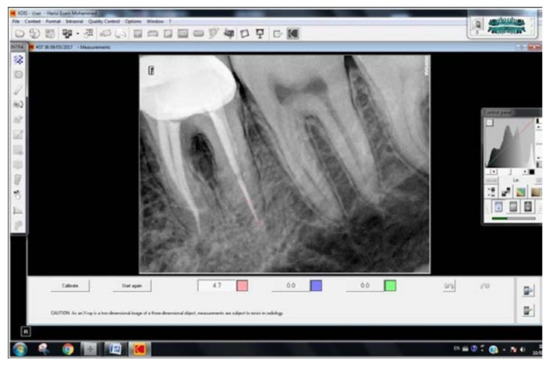

- Group I: no gap between the cemented post and the gutta-percha.

- Group II: a gap of more than 0 but less than 2 mm between the gutta-percha and the post.

- Group III: a gap of more than 2 mm between the gutta-percha and the post.